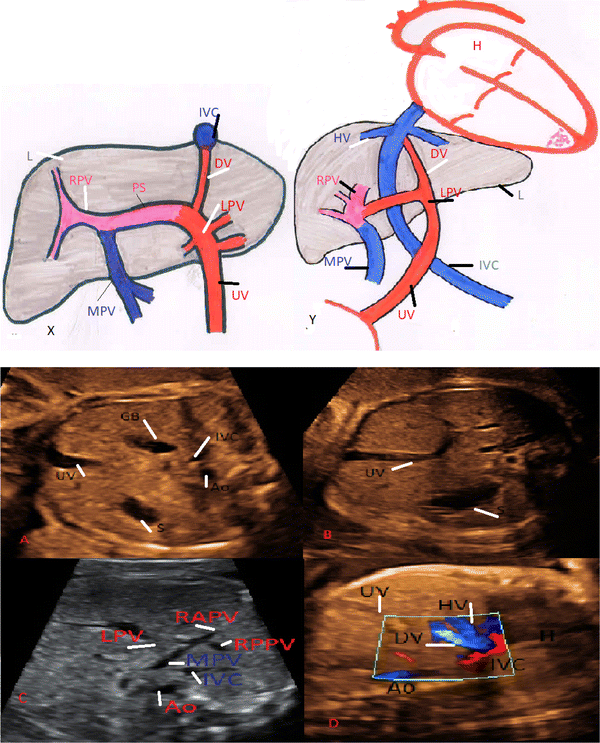

It passes through the umbilicus umbilical vein left portal vein ductus venosus middle or left hepatic vein and into the inferior vena cava. Most hernias do not hurt. A word about pain.

Sonographic Evaluation Of Umbilical Vein Springerlink

Umbilical Anatomy And Position Springerlink